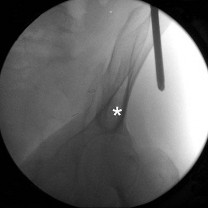

(OBQ14.208) When treating a proximal tibia fracture, the surgeon decides to (1) use blocking screws in the pr…